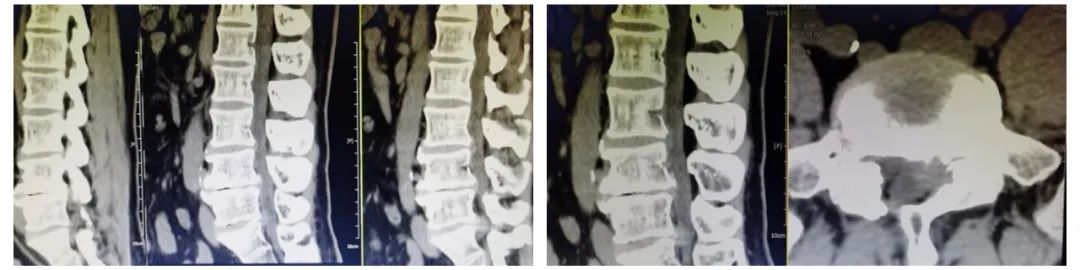

术前影像学检查:腰5/骶1椎间盘突出症术后改变,腰5/骶1椎间盘突出术后再复发